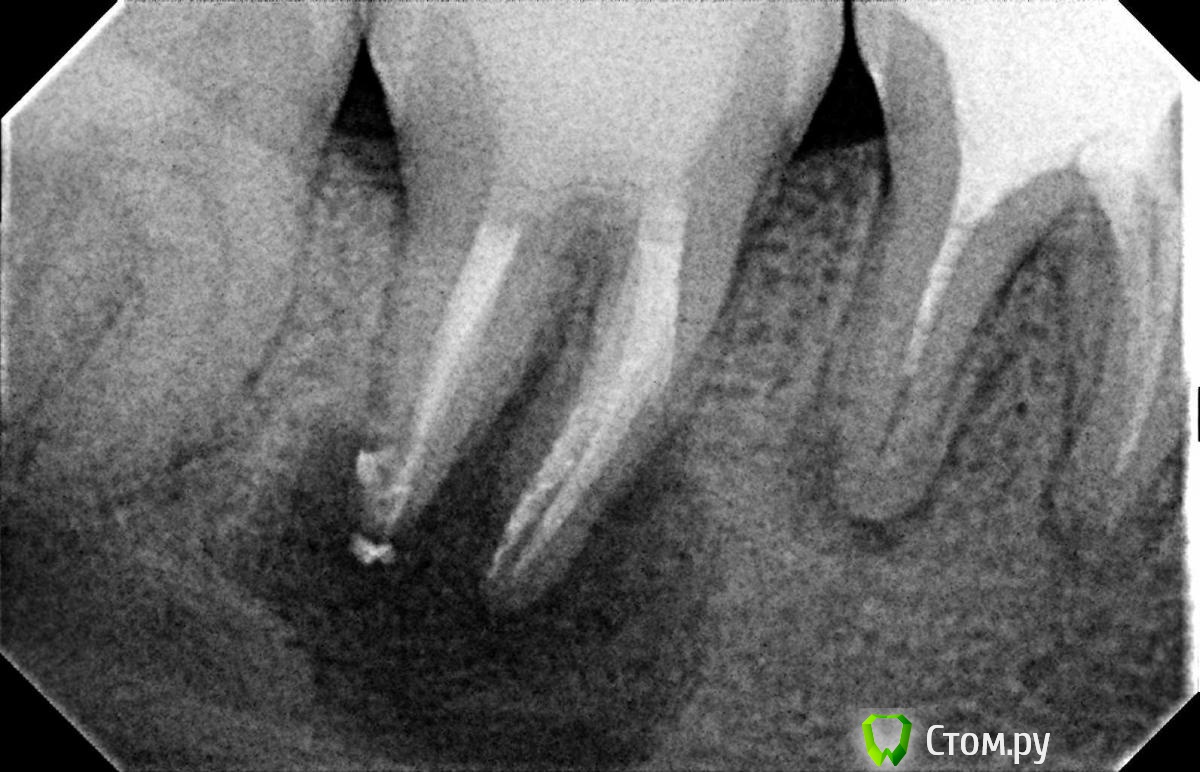

Л Ю С Я Опубликовано 10 января, 2014 Поделиться Опубликовано 10 января, 2014 .Новый кейс-совсем свежий пока без долгосрочного результата.Пациентка попала случайно удаляла зуб 28 и хирург сделал ОПТГ,где стали видны обширные периапикальные процессы в области 37 47.Побывав у меня на консультации и услышав план лечения и стоимость,пациентка решила видимо полечить подешевле.,побывав на консультациях в нескольких клиниках и в итоге даже попала к главному стоматологу нашей области. Все ей сказали что удаление онли. Вернулась,-засада была в том что план я писал исходя из ОТПГ не сделав прицел(виноват),сделав прицел понимаю что все сложнее чем я думал-ну что же тем интереснее.Переписав план лечения и подняв ценник на 40%(пациентке не оставалась выбора),начали лечение.1-посещение-ревизия пломбы.понимаю что кто то до меня с маниакальным упорством пытался запломбировать мезиальный язычный канал каналонаполнителями. Убрал два фрагмента из верхней трети мезиального язычного.2-посещение еще фрагмент из мез язычного плюс немного с дистальными поработал(их оказалось два сплит в верхней трети)3-визит обошел фрагмент в мезиальном щечном и доработал остальные каналы.4-визит -паковка.На предпоследнем снимке видны поры-допаковал(просто на финальном не очень видно)Класс! Ждем рекол через 6 месяцев. Паковка чем? Сквирт? Ссылка на комментарий

Hans85 Опубликовано 14 января, 2015 Автор Поделиться Опубликовано 14 января, 2015 Полагаю на КТ будет не такая уж радужная картинка...Чем завершено лечение? Коронка?Наконец то пациент пришел на коронку.Вот и Кт ,да заживление не 100% ,но все же . 3 Ссылка на комментарий